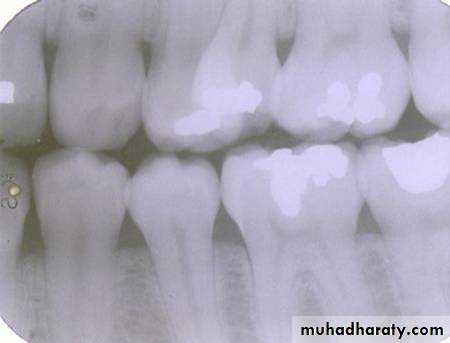

Is the maxillary second premolar (arrows) displaced to the buccal or the lingual?

premolar filmmolar film

premolar bitewing

4The tube head moves distally from the premolar film to the molar film. The second premolar also moves distally, overlapping the first molar more in the molar film. In moving from the premolar periapical to the bitewing, the tube head moves down and the premolar also moves down. The displacement is to the lingual.